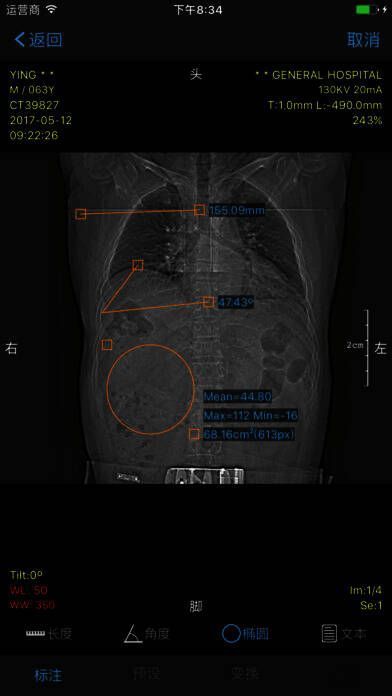

2. 多项功能,强大实用:可进行 WL、测量、角度、CT 值、旋转等操作。

- 多项功能,强大实用:可实现 WL、测量、角度、CT 值、旋转等操作。